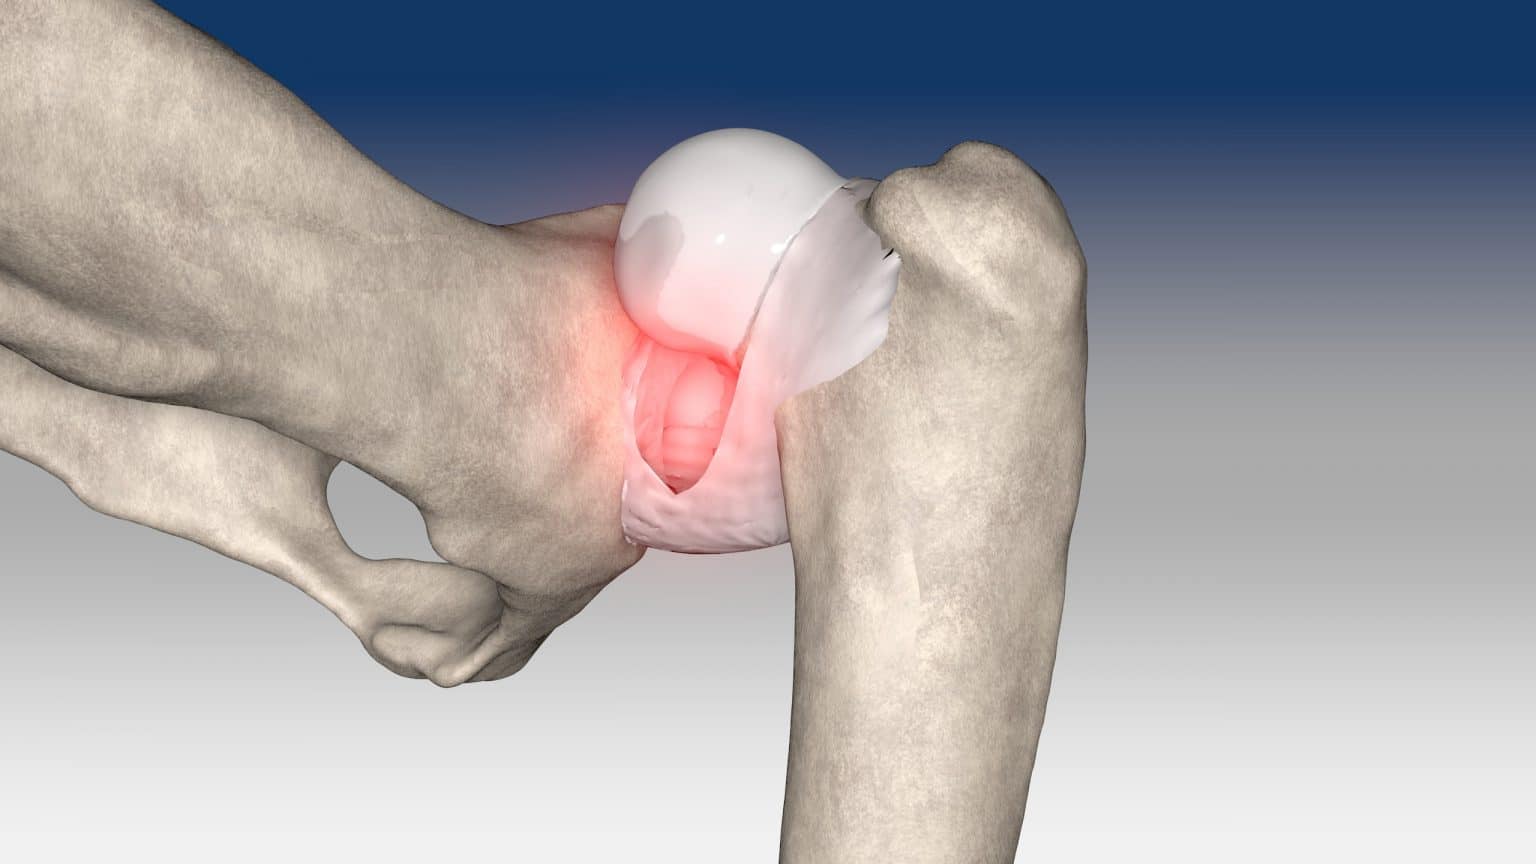

Hip dislocation : Round ligament reconstruction